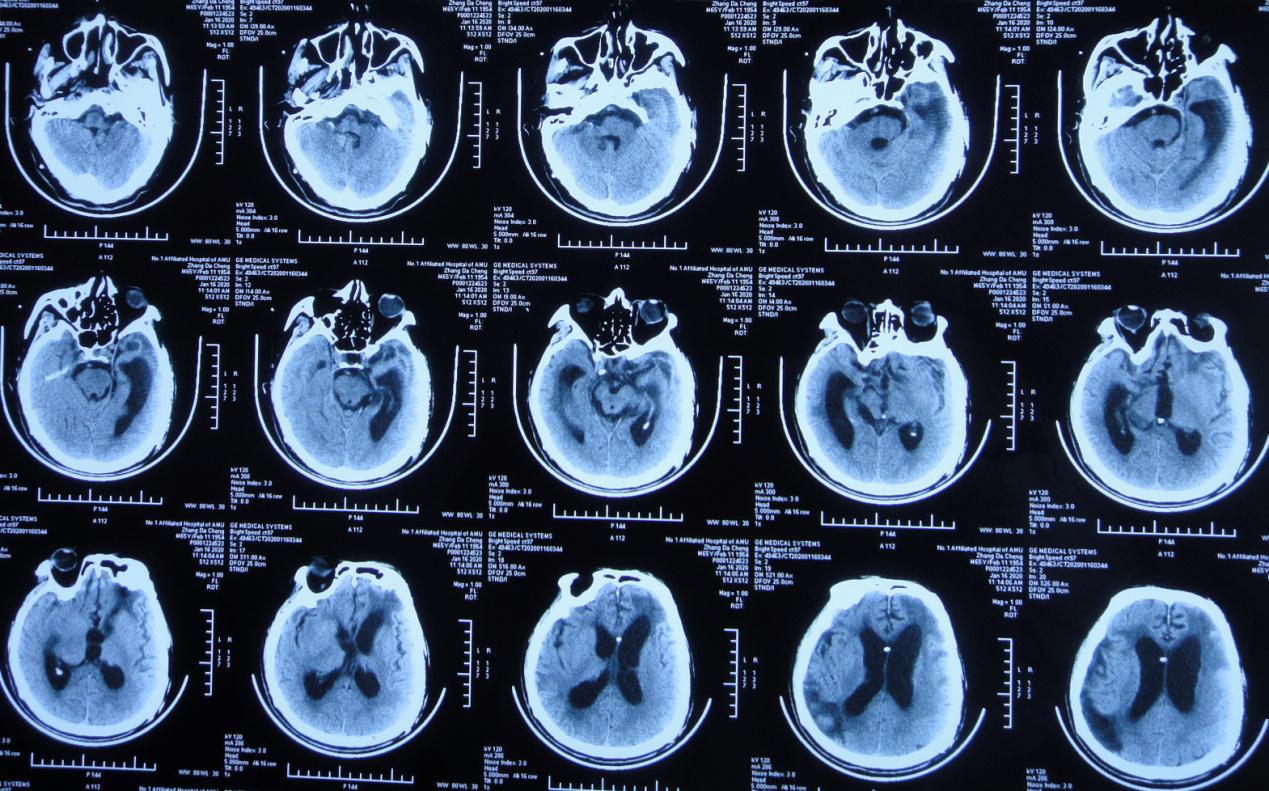

入院时:体温高达38.9℃,呈昏迷状态,疼痛刺激时四肢未见活动;颈稍抵抗,双下肢Babinski征未引出( 图-16 );头颅CT( 图-17 )示脑室腹腔分流术后改变,脑室扩张,脑室周围水肿。

图-17: 2020年1月31日头颅CT

入院第2天,即2020年2月1日行右侧脑室外引流术,术中拔除原脑室腹腔分流管,术后当日复查头颅CT( 图-18 )呈术后改变。

图-18: 2020年2月1日头颅CT术后